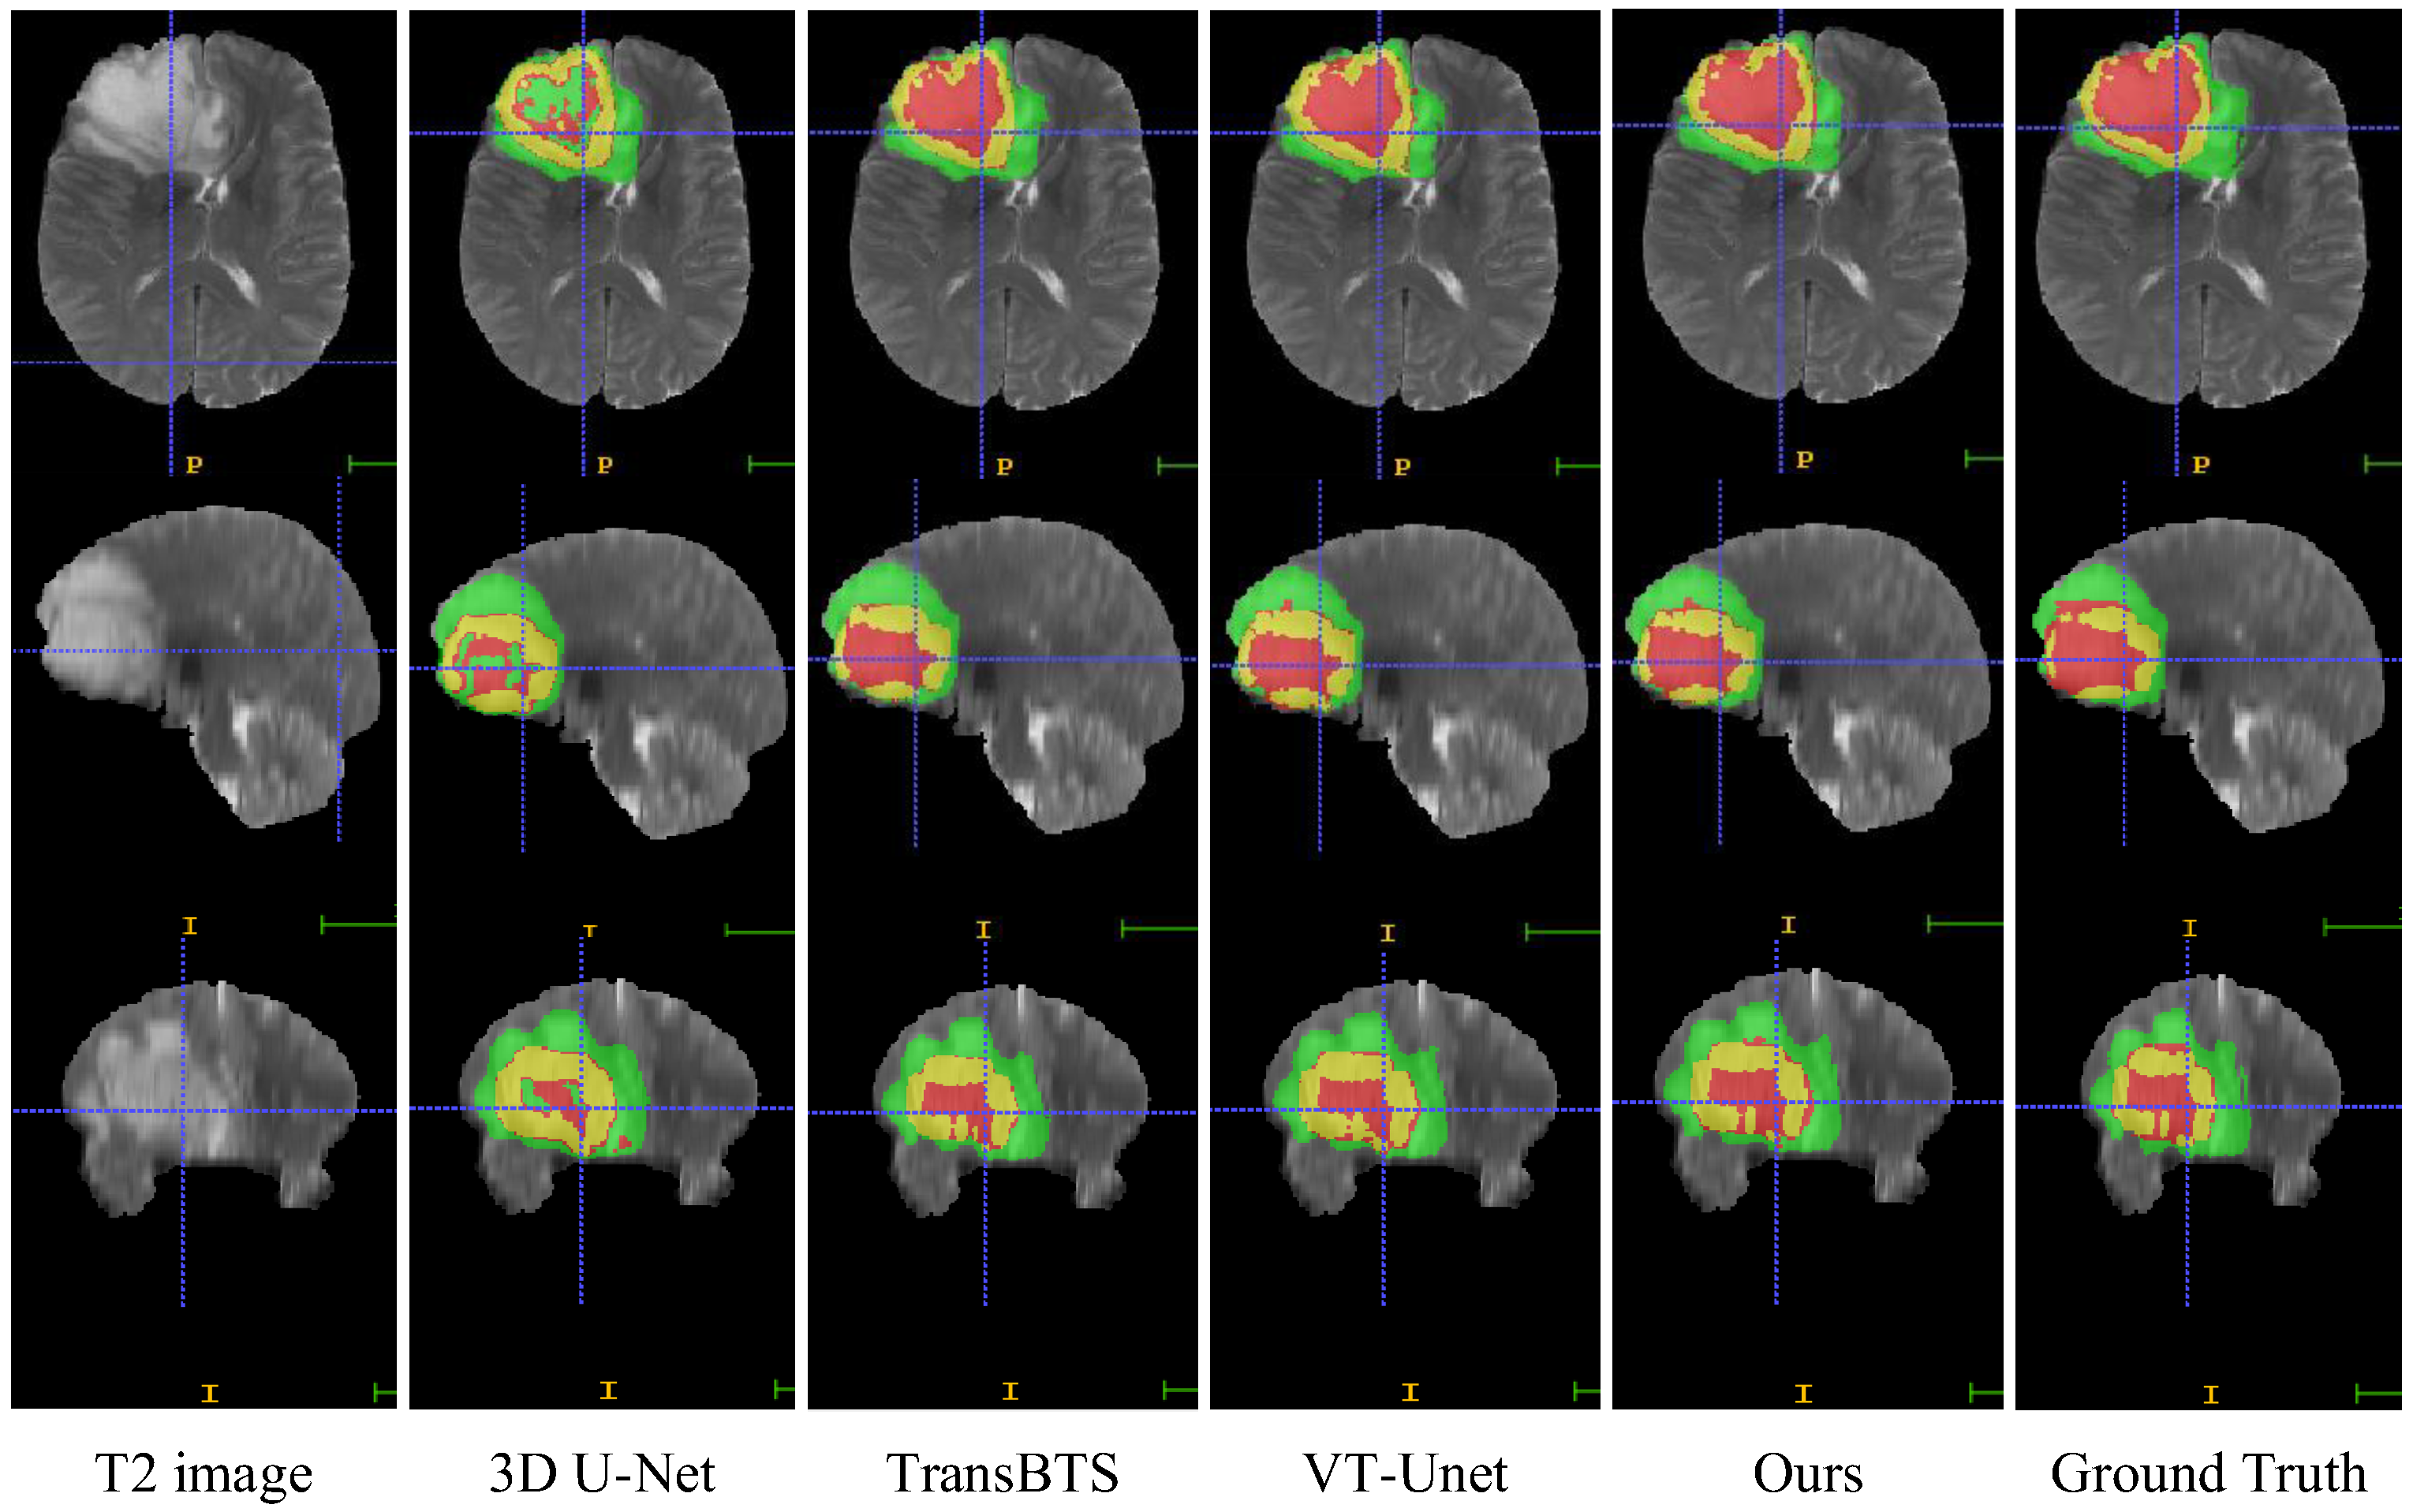

4.8. Visual Comparison

In this section, we compare the visualization of the brain tumor segmentation results between the proposed method and 3DU-Net, TransBTS, and VTU-Net, as shown in Figure 4. In Figure 6, the first row is the cross-sectional image of the brain tumor, the second row is the sagittal image, and the third row is the coronal image. For the convenience of observation, we show all three cross-sectional images and set the coordinates of the intercept point as (109, 89, 78). The red label in the figure represents the ET area, the yellow label represents the TC area, and the green label represents the WT area. It can be seen from Figure 6 that all models have the best segmentation effect for the WT region, and the segmentation effect for the two complex edges of ET and TC is very different. Compared with Ground Truth, our model is more accurate for the segmentation results of edge details.

Figure 6. Visual comparison of MRI image segmentation results.